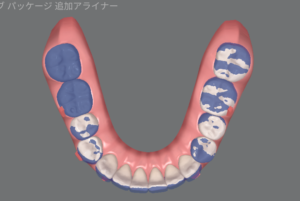

実際にオーバーコレクションステージを使うとどんな動きをするのでしょうか?

青がNo.8の歯並び、白がNo.11の歯並びです。

上下とも前歯がギュッと下がっていますね。

No.8の時点で余分な隙間がなければ、オーバーコレクションステージは使わなくて良いのですが、通常のアライナーと違いがあるのか気になるので使ってみたいなぁと思っています!